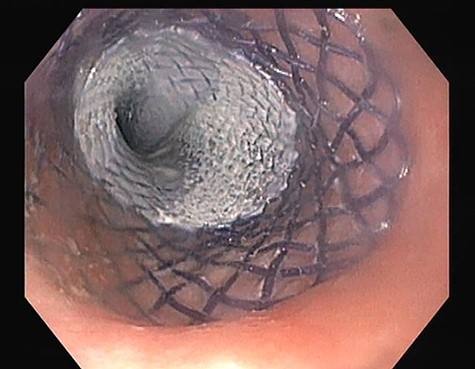

A last endoscopic treatment attempt of the oesophageal fistula was made 8 weeks after hospital discharge (October 2015), whereby a covered biodegradable stent was used and stabilized in place with clips (see Fig. 6). The success of the last endoscopic approach was confirmed with upper GI contrast swallow study (see Fig. 7). Oral feeding was reintroduced with tolerance.

Esophagogastroduodenoscopy image showing a covered biodegradable stent occluding the proximal orifice of the oesophageal fistula.